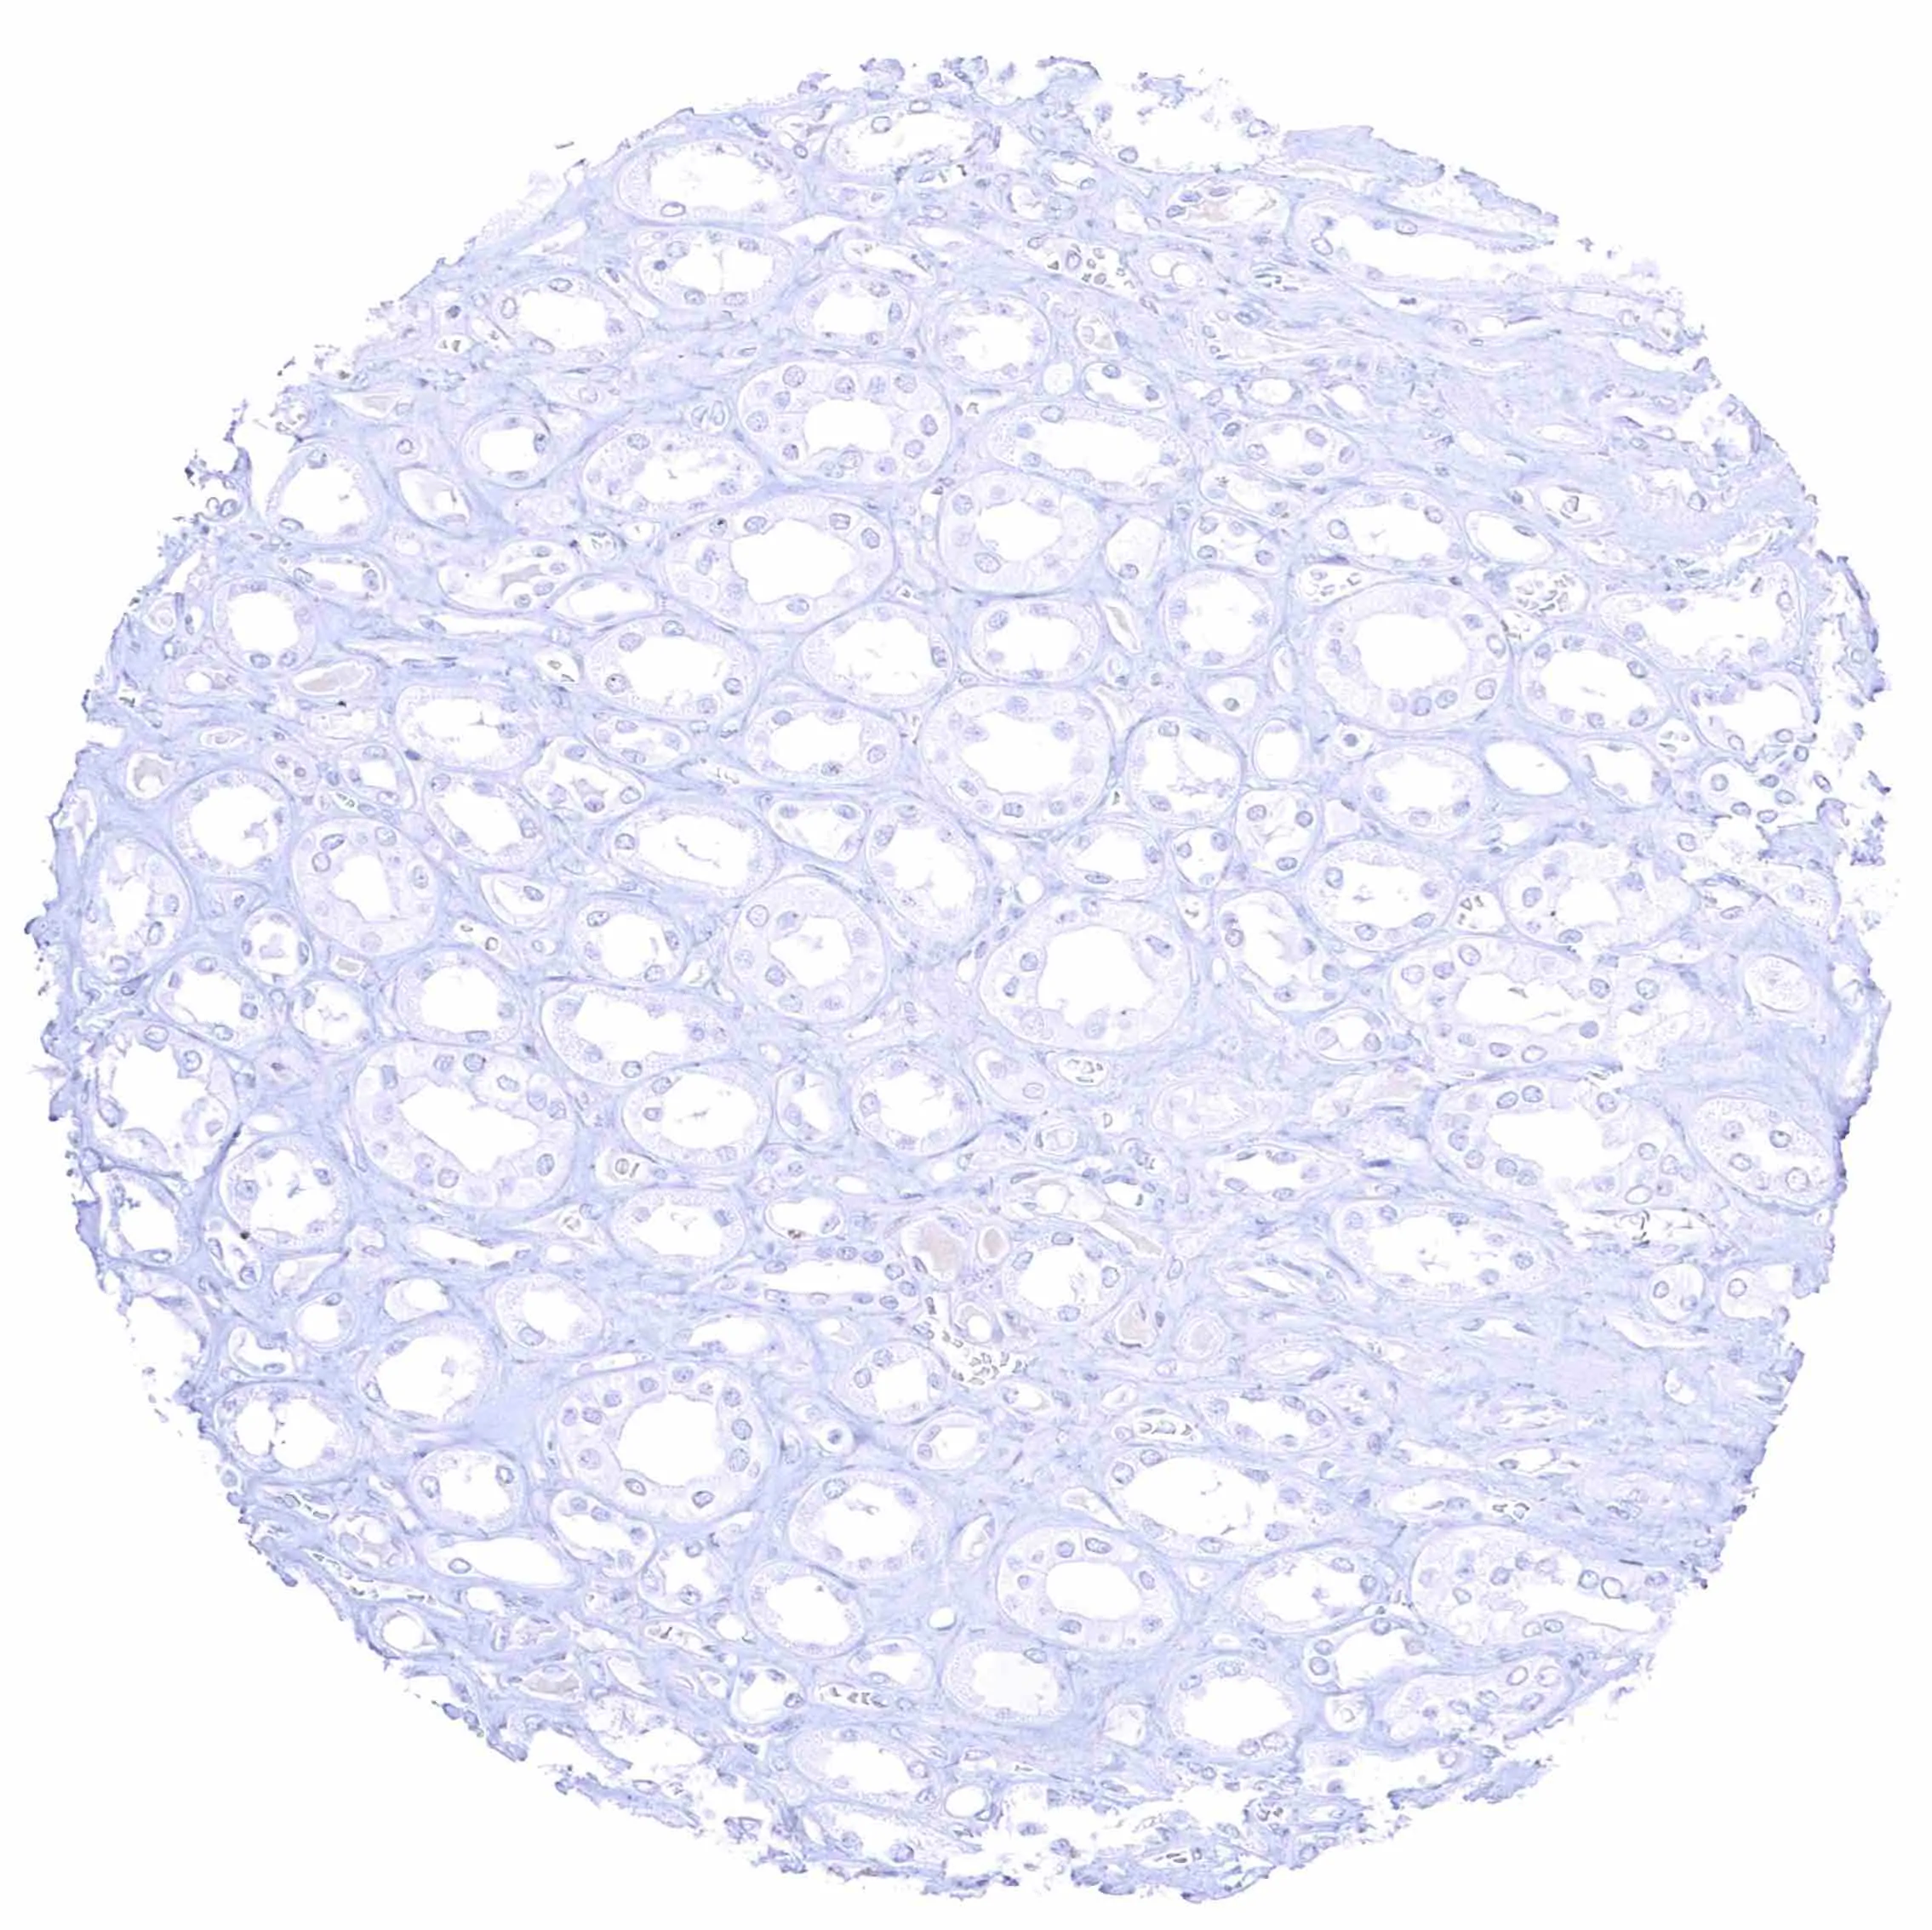

Fat